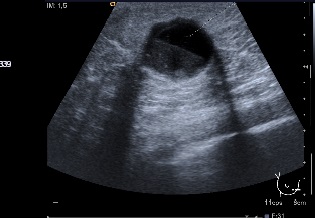

An eighty-one year old patient consulted for an emerging nodule in the right breast without any family or personal history of interest. On physical examination, the patient had a nodule of 20 mm in the lower inner quadrant of the right breast. In the mammogram a nodular image was observed that with ultrasonography was identified as a cyst containing clear borders and good sound transmission (Fig. 3): the FNA evidenced papillary epithelial proliferation.